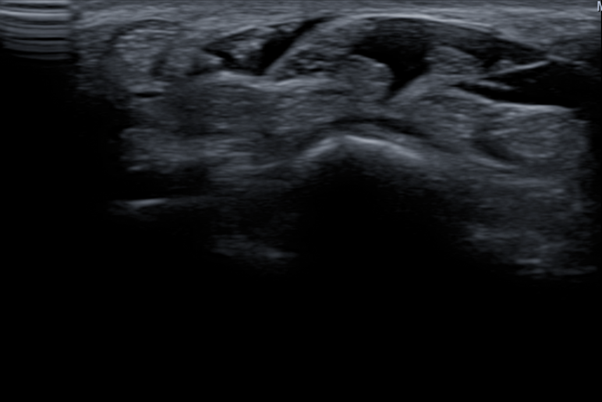

그래서 바로 초음파 검사를 진행했습니다.

초음파로 손목 부위를 자세히 살펴보니,

역시나 정중신경이 지나가는 터널 부위에

염증으로 인한 부종이 뚜렷하게 보이더라고요.

그림9.png 촬영 일시 2025.05.06

<fig 1. 손목터널증후군으로 진단된 초음파 영상>